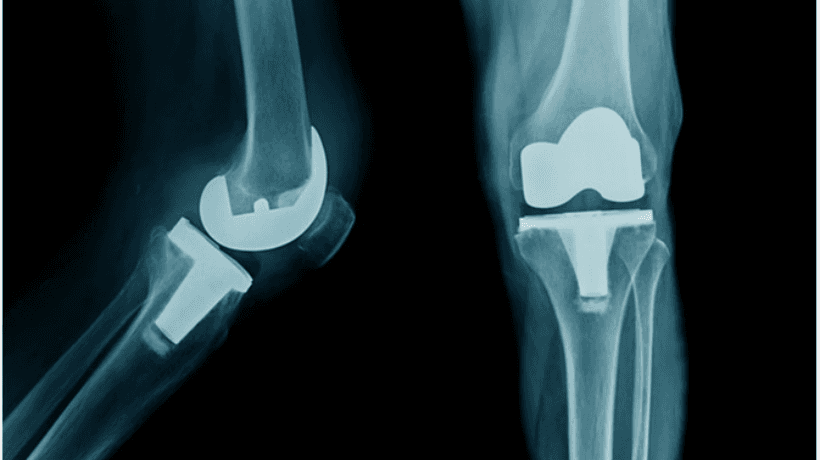

Knee surgery typically refers to total knee replacement which can either be performed in the old-fashioned open manner or else by the less invasive modern technique known as knee arthroscopy.

An Orthopedist employs implants and implements various modern techniques to provide necessary help to the patients. Following are the types of knee replacement surgeries performed:

- Total knee replacement

- Partial / Uni compartmental knee replacement

- Kneecap replacement (Patellofemoral Arthroplasty)

- Complex or revision knee replacement

- Knee ligament reconstruction